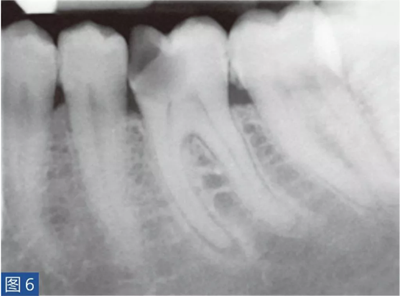

致密性骨炎(圖6 和7)是AAP 的一個(gè)變種。造成致密性骨炎的原因是,根尖周組織受到長(zhǎng)期的持續(xù)性刺激。臨床檢查時(shí),對(duì)敏感測(cè)試、叩診和觸診可能有反應(yīng),也可能無(wú)反應(yīng)。放射學(xué)檢查,牙齒的根尖周圍存在彌漫性的致密阻射影像。

圖6:36 牙齒CO。術(shù)前X 線片。患者因牙齒36 充填物脫落而前來(lái)就診。X 線片顯示遠(yuǎn)中根的根尖區(qū)有白色阻射影像。近中根的根尖區(qū)顯示在白色阻射區(qū)內(nèi)有透射影像。